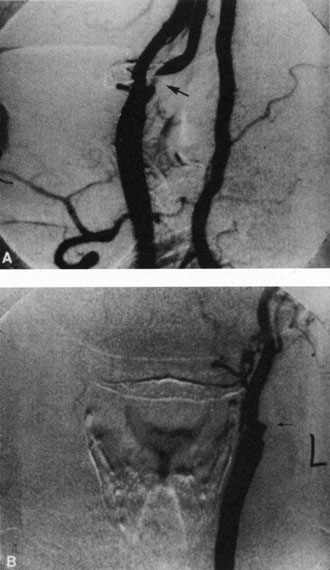

Obstruction of one of the posterior ciliary arteries may result in a whitening of the area of the retina supplied by the involved posterior ciliary artery and the subsequent appearance of patchy pigmentation in the same area. However, in patients with anterior ischemic optic neuropathy secondary to temporal arteritis the retina may appear normal (Fig. 5). In the case of either the medial posterior ciliary artery or the lateral posterior ciliary artery, the area involved is the size of approximately half of the choroid.121–123 In the case of a long posterior ciliary artery, the temporal side of the eye including the macula is involved.121

Fig. 5. A: Ischemic optic neuropathy in a patient with giant cell arteritis. B and C: Intravenous fluorescein angiography demonstrates delayed filling of the lateral posterior ciliary artery.

We have seen several patients with anterior ischemic optic neuropathy with suspected temporal arteritis where the Westergren sedimentation rate and C-reactive protein were normal and the intravenous fluorescein angiogram helped confirm the diagnosis (Fig. 5).